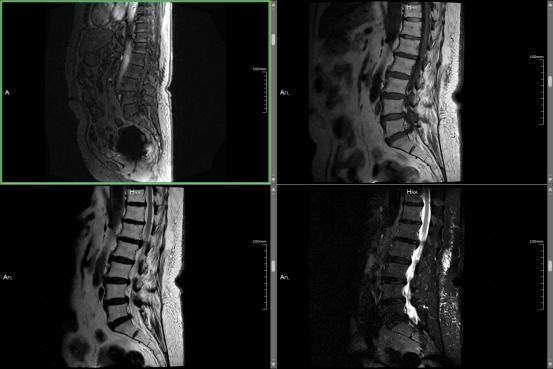

【医声守护·科普】第234期:有避孕环可以做腰椎核磁共振吗?